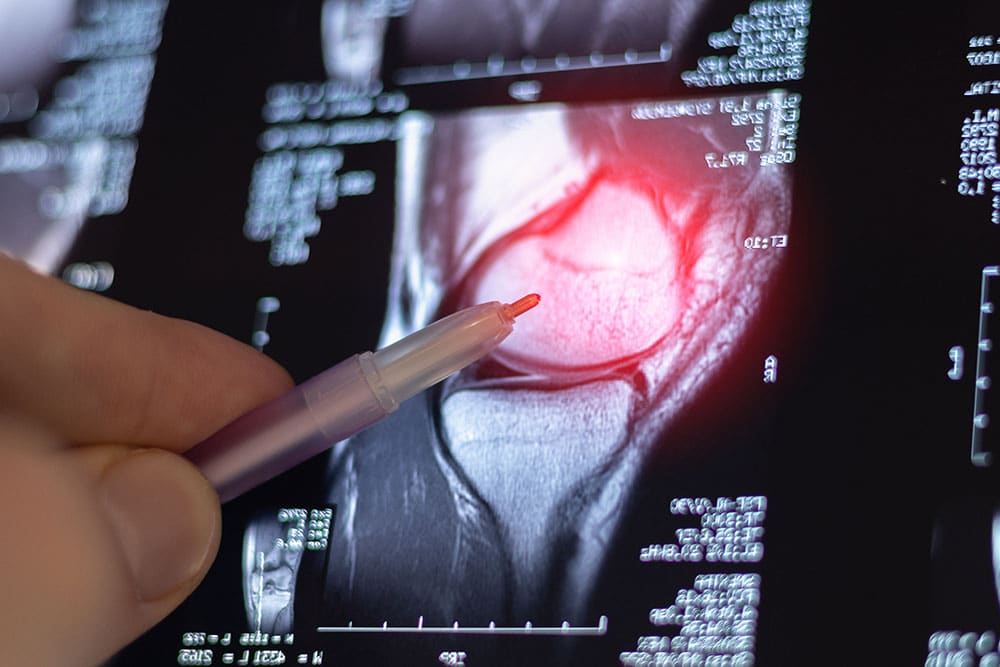

In the lead up to the operation, your specialist will go through a final round of assessment and planning with you. This usually includes revisiting your symptoms, reviewing the most recent X-rays of the knee, and in some cases other imaging such as MRI or CT scans when needed. These help confirm which part of the joint will be treated and guide how the implant should be best positioned, so the surgical plan is tailored to your knee.

Your specialist will first check to see if your symptoms fit a single compartment problem, rather than wear across the whole knee. This starts with a physical examination to assess where the pain is coming from, how stable the knee feels under load, and whether alignment is still reasonably maintained. X-rays are then reviewed to confirm which compartment is affected and how localised the damage is. If more clarity is needed, imaging such as MRI or CT scans can help assess cartilage damage and ligament health. From there, the decision comes down to whether the rest of the joint can still be preserved for a partial approach.